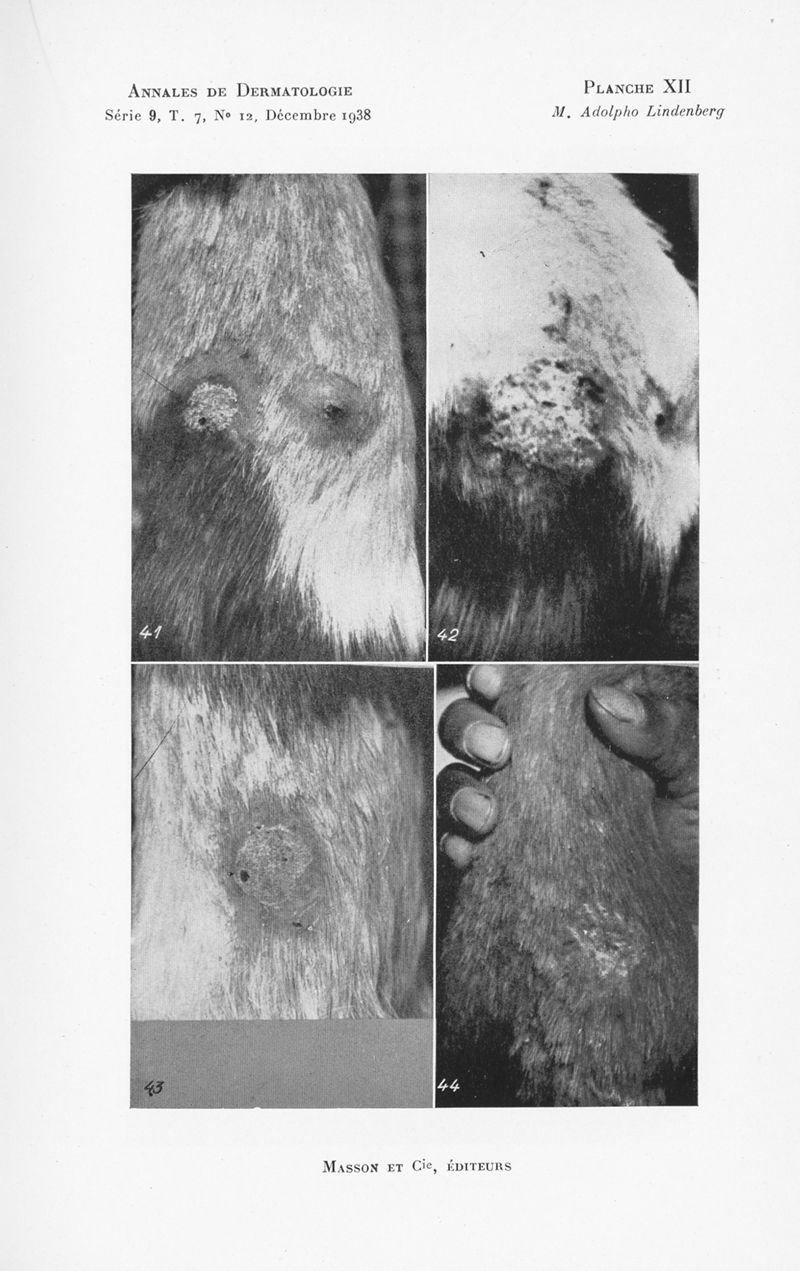

Annales de dermatologie et de syphiligraphie

7ème série, tome IX. - Paris : Masson, 1938.